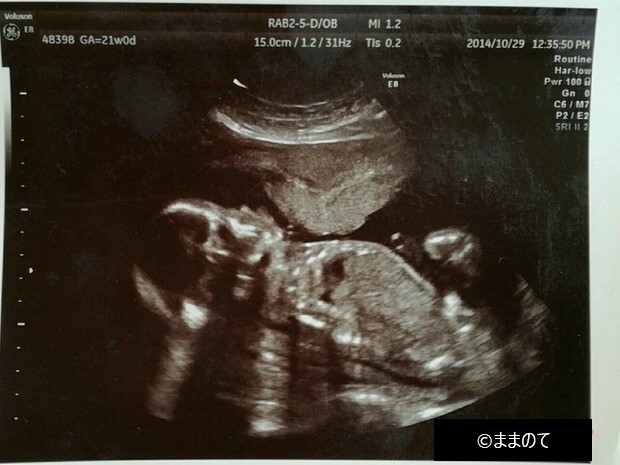

【女の子のエコー】妊娠21週

上のエコー写真は「おそらく女の子だろう」と医師が判断したときのものです。エコーの際に赤ちゃんが横向きだと、股間付近に突起物があるかないかを判断しやすいため、性別が判定しやすいといわれています。今回のエコー検査では、突起物が確認できなかったため女の子という判定がされました。